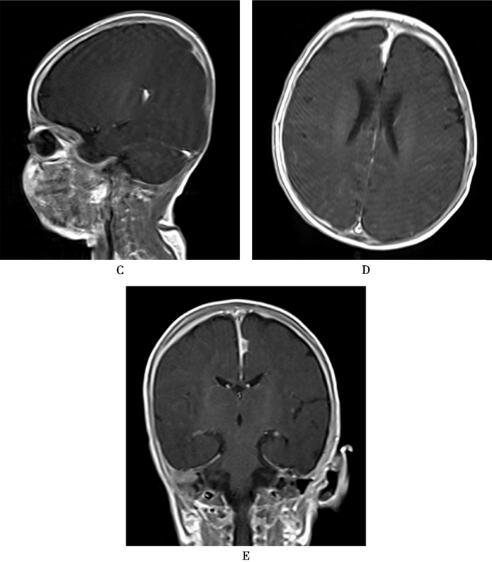

图1 特发性肥厚性硬脑膜炎

平扫灰白质界限欠清晰,增强后颅内硬脑膜明显广泛增厚强化,颅脑实质内未见明显异常强化灶